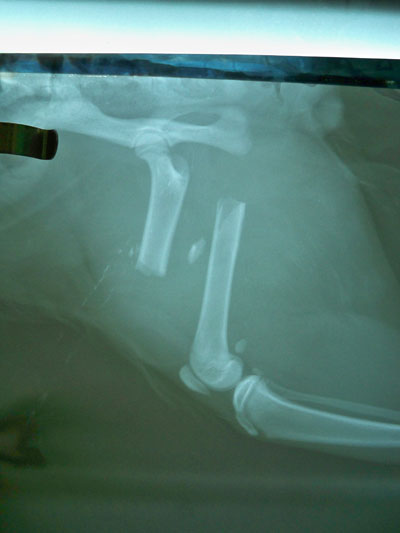

Γάτος ηλικίας 7 μηνών με κάταγμα μεσότητας διάφυσης μηριαίου οστού .Πραγματοποιήθηκε ορθοπεδικό χειρουργείο με μεταλική πλάκα κοχλίες και ορθοπεδικό σύρμα. Η αποκατάσταση ήταν 100% τα υλικά αφαιρέθηκαν 3 μήνες μετα .